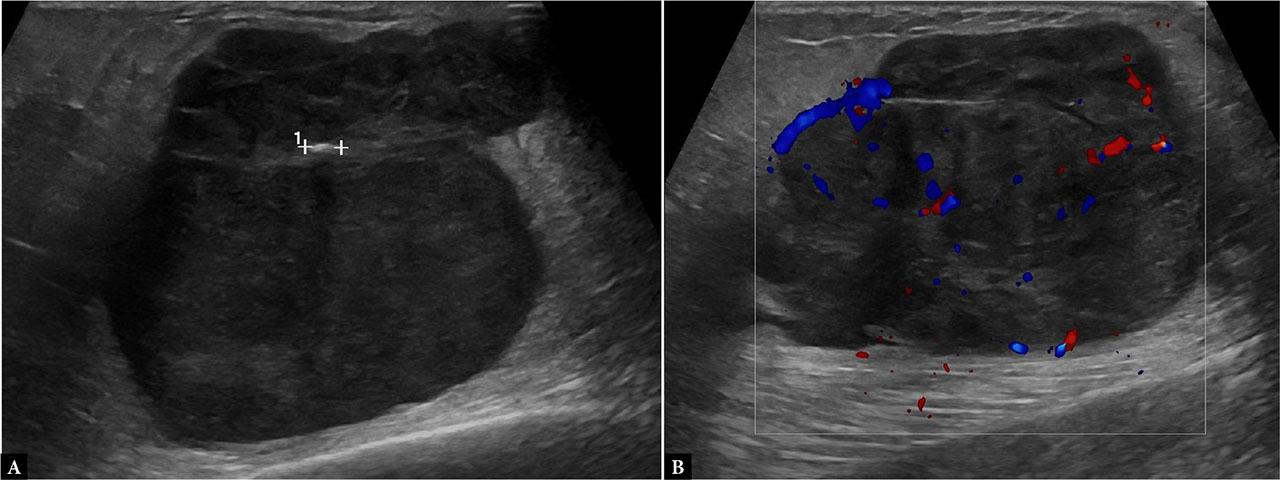

An initial bedside US of the chest wall was performed to investigate the etiology of the swelling. The findings were highly suggestive of a subacute hematoma, based on the clinical timeline (approximately one week after onset) and characteristic sonographic features, including internal echogenic sediment, fine septations, and a fluid–fluid level, with no detectable internal vascularity on CD. However, since an evolving infectious component could not be excluded, clinical and laboratory monitoring was advised, along with follow-up imaging. A repeat US examination performed a few days later demonstrated evolution of the known lesion: the collection was now more disorganized in appearance, consistent with clot lysis and organization, and had increased in size. These findings were compatible with a hematoma in evolution (Fig. 2). In this case, the increased size of the lesion and the patient’s altered hemoglobin level were the determining factors for proceeding with contrast-enhanced CT to exclude active contrast medium spread.

Ultrasound of the right pectoral region showing a large heterogeneous subfascial (yellow arrow) intramuscular (yellow bracket) collection (12 × 6 × 12 cm) without internal vascularity on CD, consistent with a subacute iatrogenic hematoma (A, B, C). Follow-up US performed one week later (D) demonstrates increased disorganization, internal echogenic strands, and persistent absence of vascular signal, confirming hematoma evolution

Educational tip: Use a convex probe for deep or bulky lesions. In subacute or organized hematomas, echogenic sediment and internal lysis may be observed. Always compare lesions over time for evolution. The lesion’s location beneath the fascial plane helps differentiate it from superficial collections such as seromas.

Clinical correlation: The temporal link with catheter removal and progressive swelling makes an iatrogenic hematoma the most plausible diagnosis. Anticoagulation status (not specified but crucial) would further increase the bleeding risk.